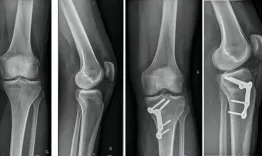

A 68-year-old woman has been suffering from mechanical bilateral knee pain for the past 6 years. The x-rays reveal complex right knee arthritis with ligament deficiency. How would you classify it and how would you manage this condition?

Management of complex knee arthritis with ligament deficiency

Laurent Bedes